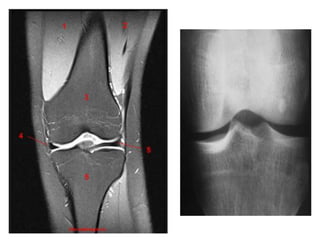

RM X RADIOGRAFIA

LOCALIZADOR

PLANEJAMENTO SAGITAL

PLANEJAMENTO CORONAL

PLANEJAMENTO AXIAL